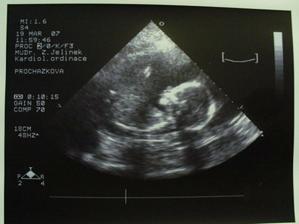

SRPŇÁTKA 2007 - fotky UTZ

album věnované mimískům, které se narodí v srpnu 2007 a jejich maminkám ze "Společného termínu SRPEN"